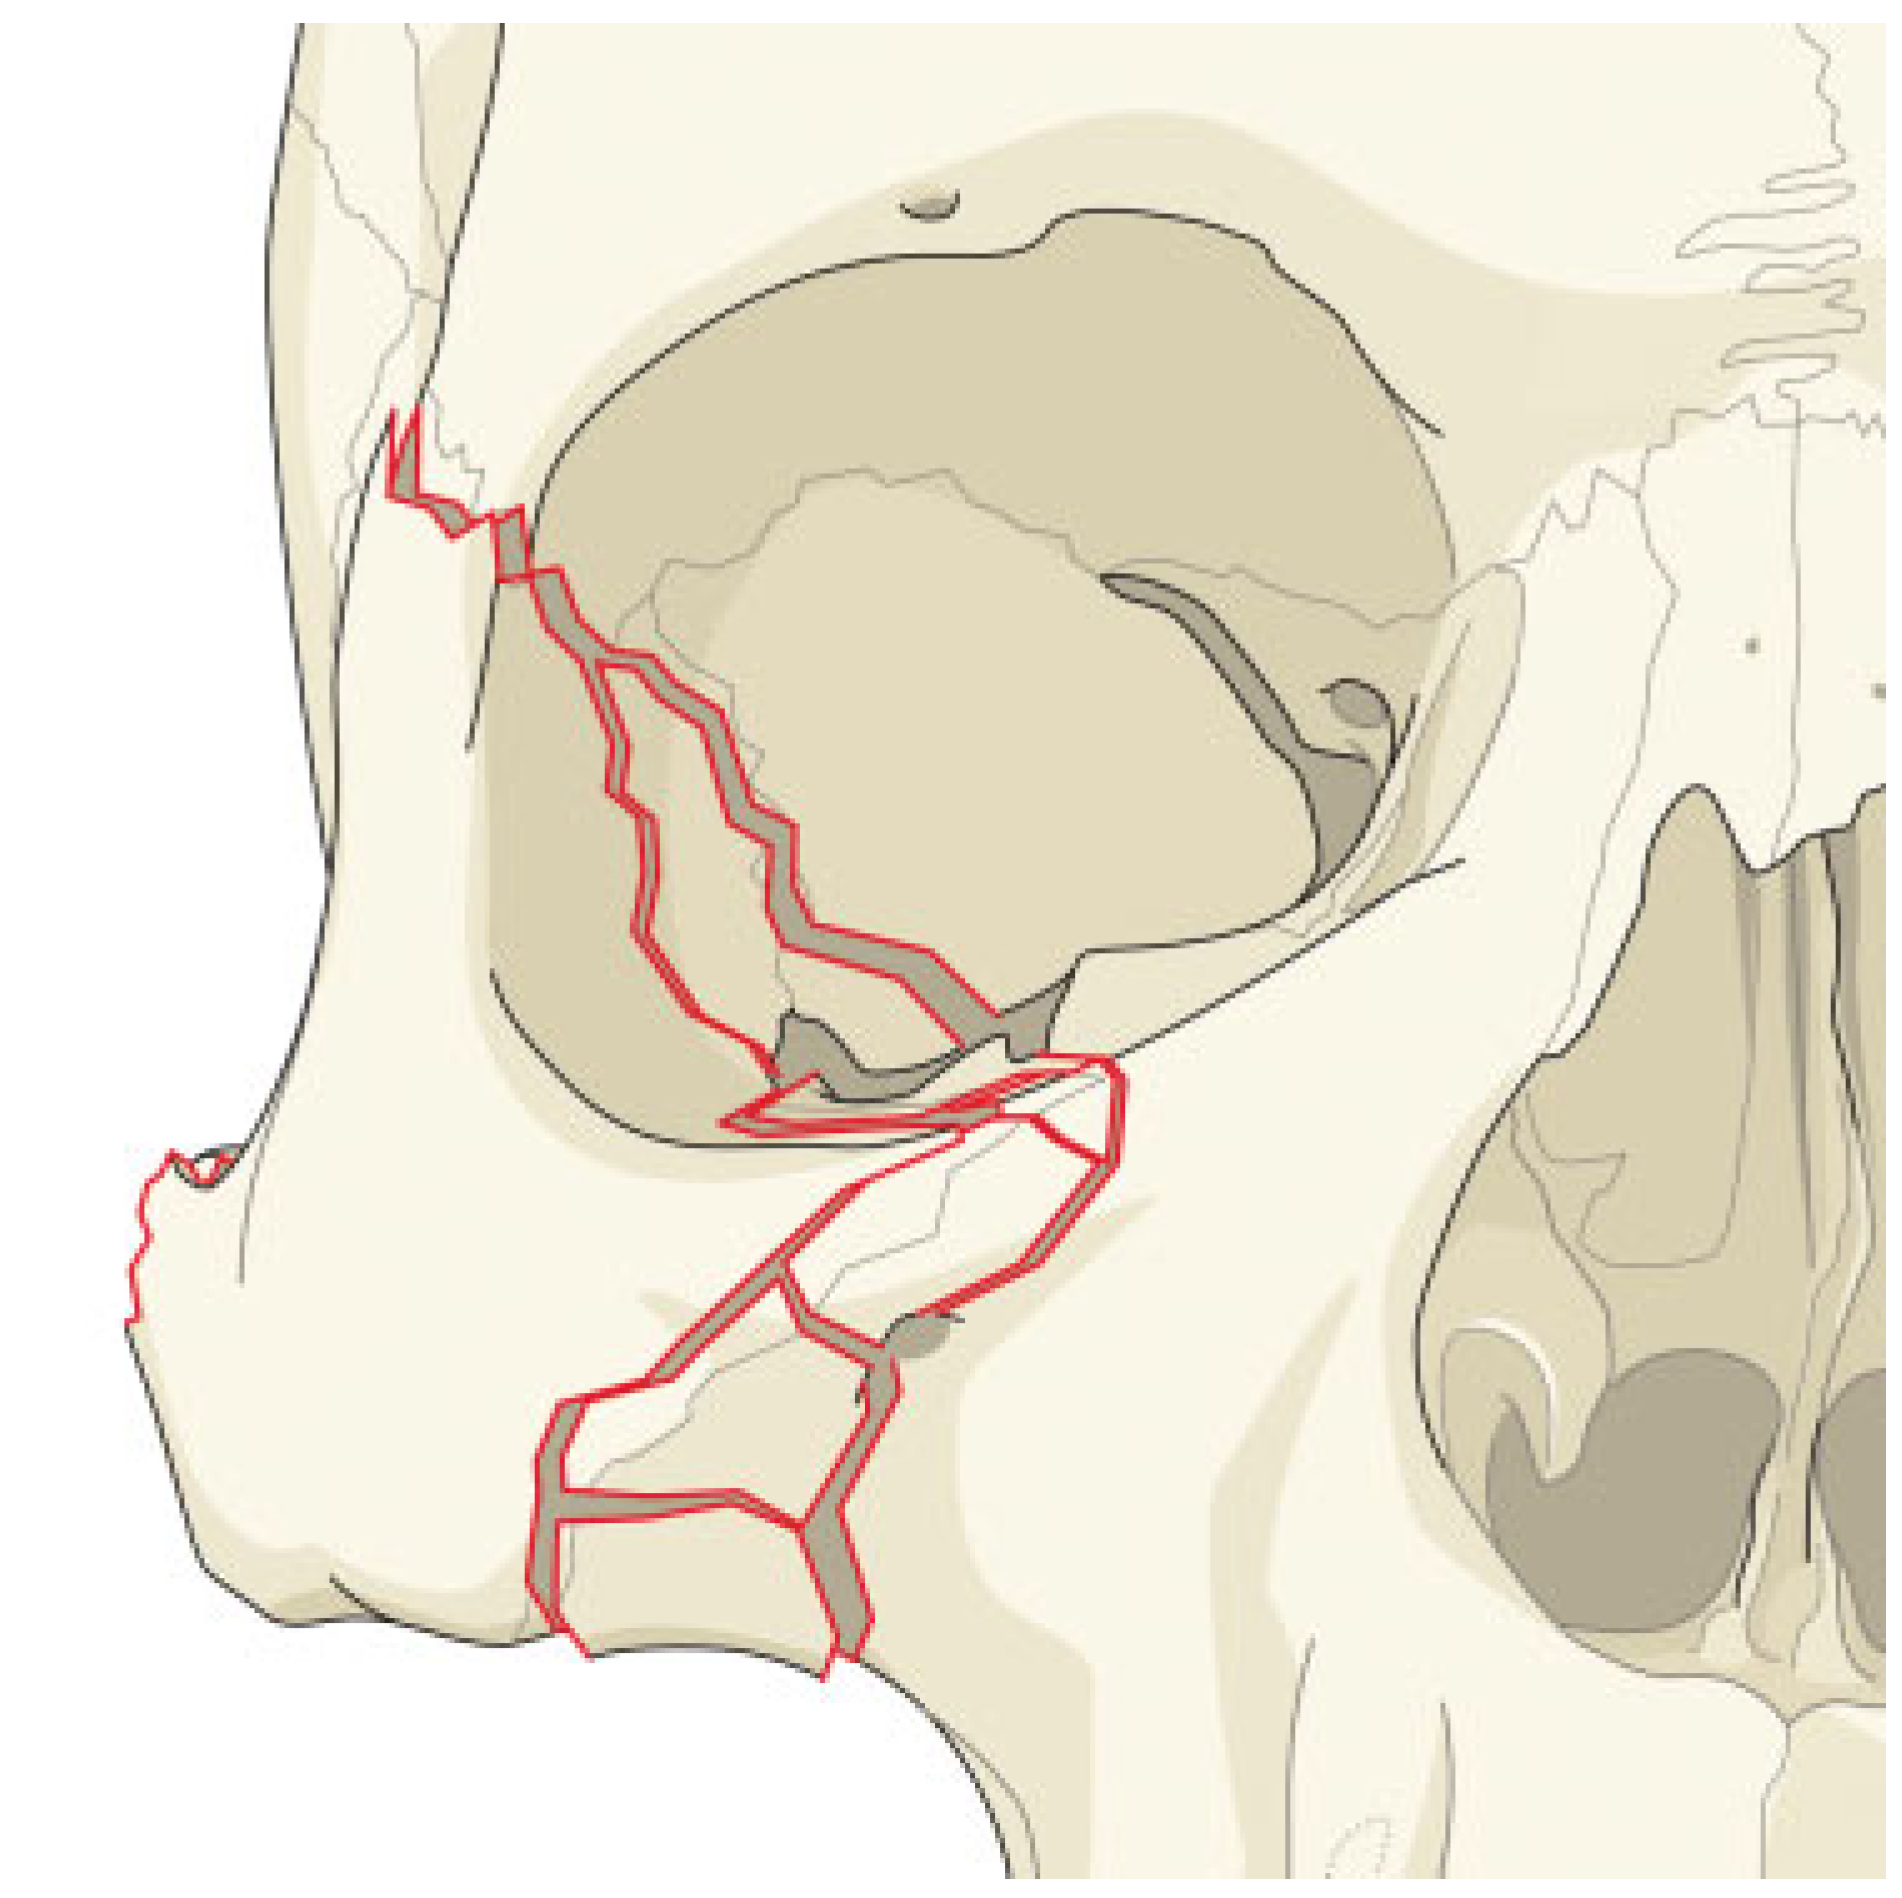

In cases where there is a simple fracture of the zygoma, and no comminution of the various zygomatic processes, the surgeon may be fairly certain of attaining a proper reduction of the zygoma without exploring the LOW (Figure 3). In cases where the zygomatic processes are comminuted, it will be much more difficult in assuring the three dimensional reduction of the zygoma and reduction will be less exact [6]. In these patients, dissection of the LOW, to confirm the proper alignment of the greater wing of the sphenoid and the zygoma, may be much more important (Figure 4).

Figure 3.

Simple fractures at the zygomatico processes and lateral orbital wall.